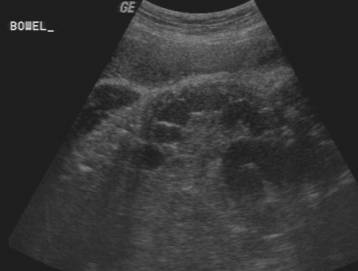

The Presacral Pseudomass.

Axial scans through the rectum can give the spurious impression that a presacral mass i.e. sacrococcygeal teratoma or anterior meningocele is present. The transducer needs to be rotated into an oblique position which will demonstrate the typical appearance of the rectosigmoid colon.

Do not mistake normal colon for a pseudomass.

6.3% of normal third trimester fetuses may have a hypoechoic presacral mass measuring 15-30mm. This represents the meconium filled rectum in the term fetus.